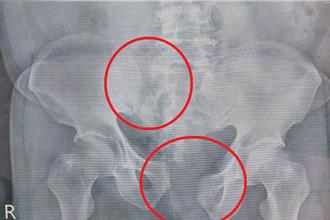

• 7旬翁墜3樓骨盆碎!醫院「神救援」 險休克到康復只花1周

7旬翁墜3樓骨盆碎!醫院「神救援」 險休克到康復只花1周

苗栗縣72歲吳先生不慎從3樓高墜落,造成不穩定骨盆骨折及薦椎骨折並伴隨骨盆腔血管破裂,經大千綜合醫院跨科別外傷團隊緊急救治,成功止血、手術復位,最終康復出院,恢復正常生活。